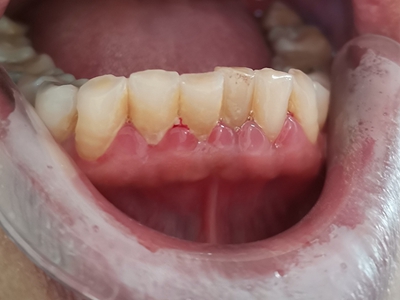

牙龈炎是发生于牙龈组织的炎症,患者可出现牙龈出血伴肿胀、发红、正常形态改变和偶尔不适等症状。本病主要由口腔卫生状况差导致,包括口腔不洁、牙菌斑等,诊断依据临床检查,治疗包括专业牙齿清洁和加强家庭口腔卫生。

牙龈炎可先引起牙齿与牙龈之间的沟(龈沟)加深,然后牙龈充血,炎症围绕一个或多个牙齿,伴牙龈乳头肿胀和易出血。一般无痛,可自行消退,也可维持轻度炎症数年。